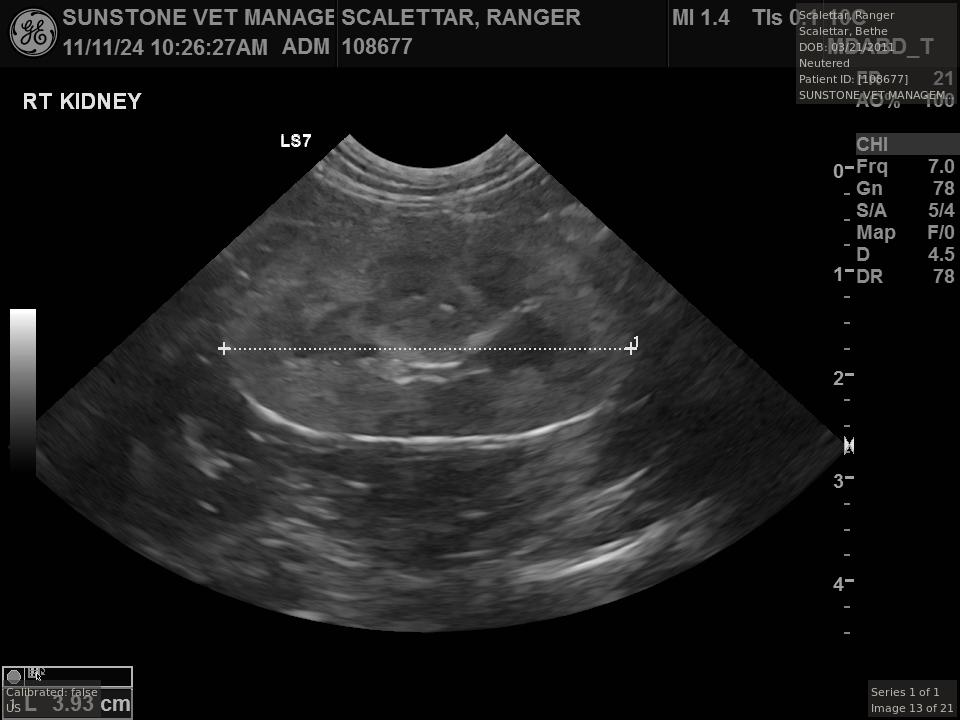

The veterinarian generated a series of images showing different organs and substructures by

changing the position and orientation of the ultrasound transducer. The images were collected

in a defined order, which is repeated from patient to patient, ensuring that nothing is missed. In

Ranger's case, the sonographer collected about twenty images during an examination that

lasted about fifteen minutes.

The sonographer stated that Ranger's ultrasound images were largely normal for an older cat. In particular, they show changes in the kidneys that are commonly noted in geriatric cats and that reflect a risk for the development of chronic kidney disease. However, the images did not show any significant abnormalities in Ranger's stomach, intestines, and associated lymph nodes. Nonetheless, the results did not rule out recurrence of Ranger's small cell lymphoma.